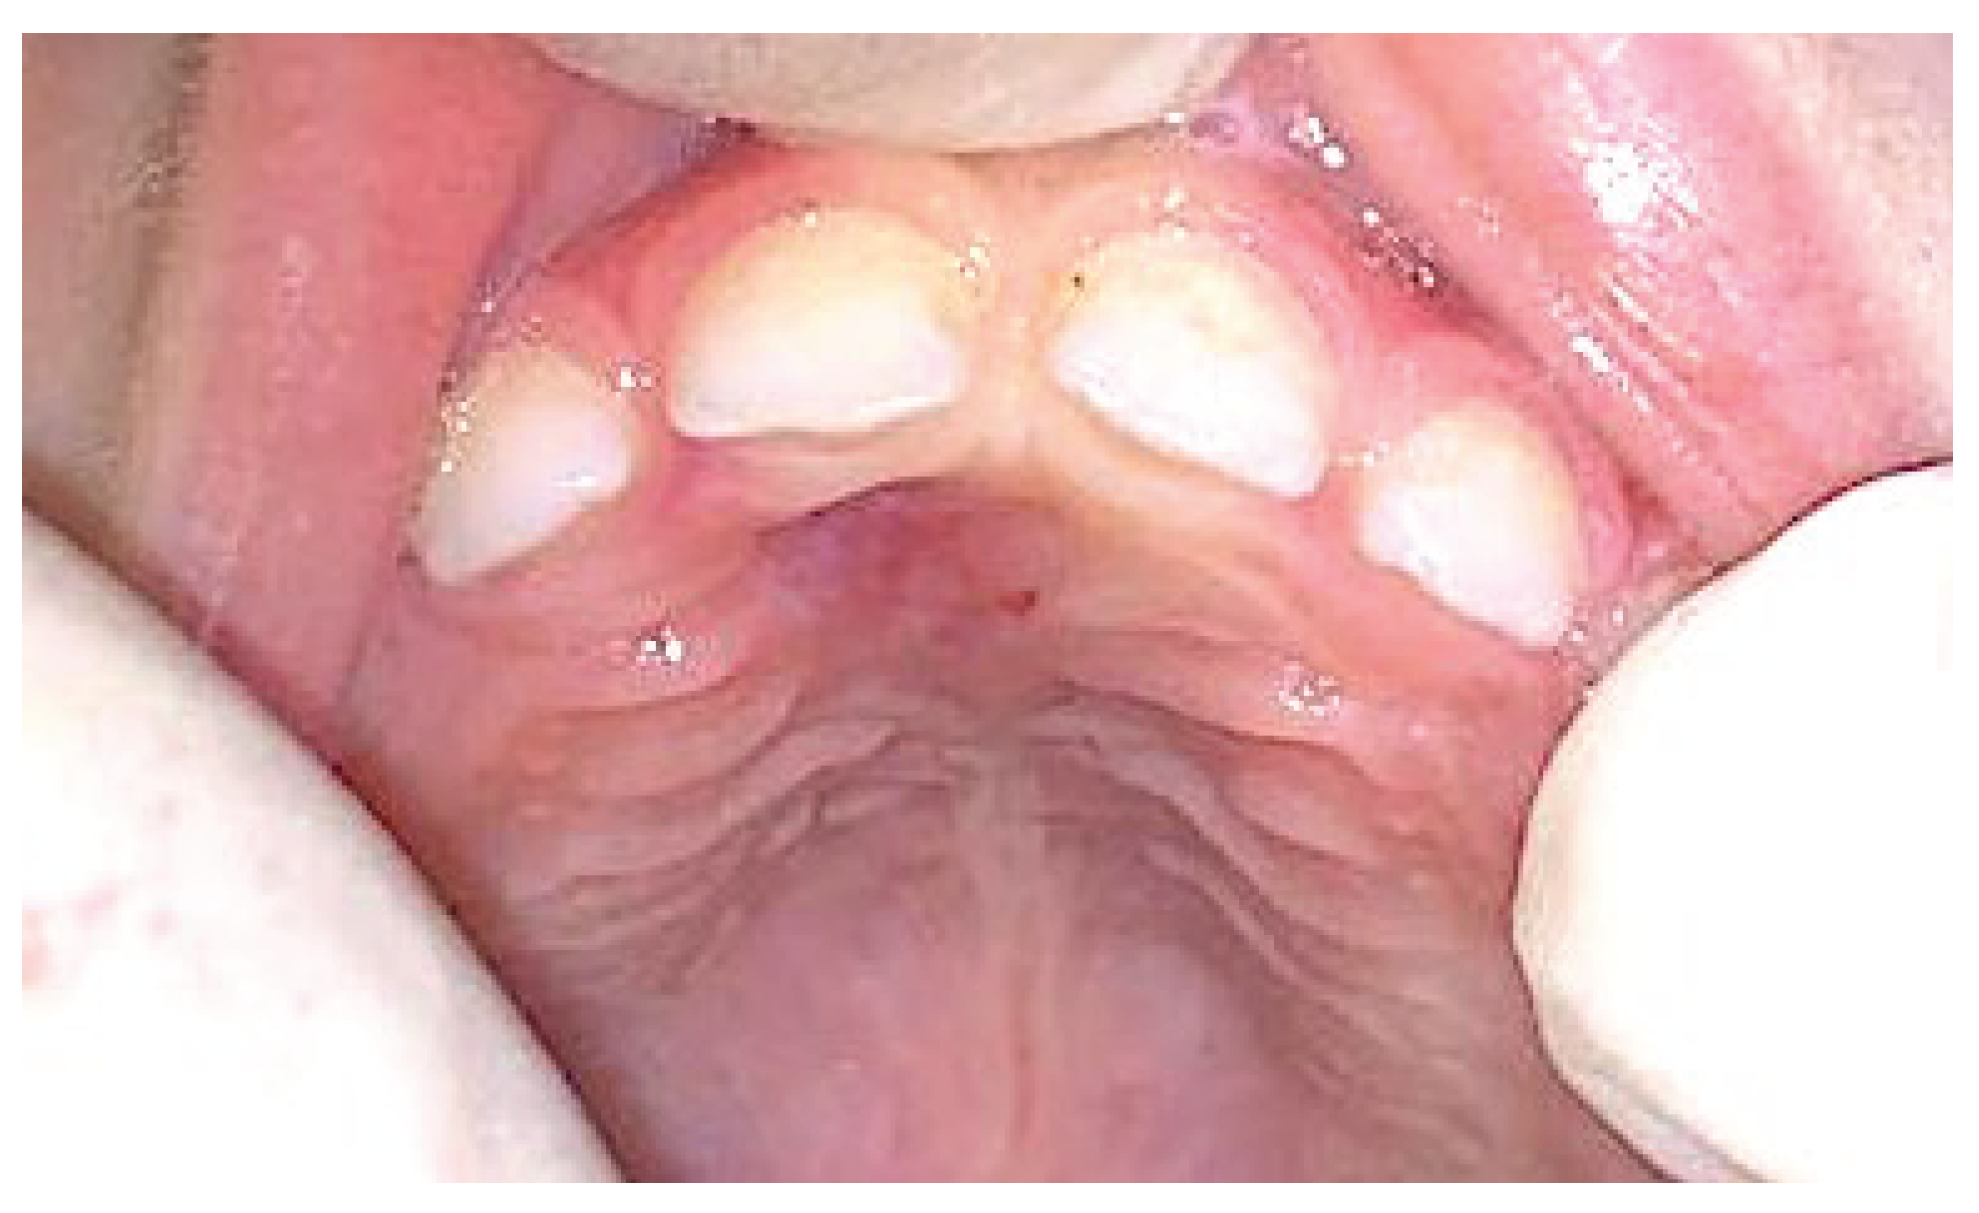

2015 | 1 | 11 | F | Anterior maxilla Right canine region |

4 × 3 cm | sessile exophytic lesion without changes in color, indurations, or ulceration. | OPT CT |

General anesthesia | POF | No |